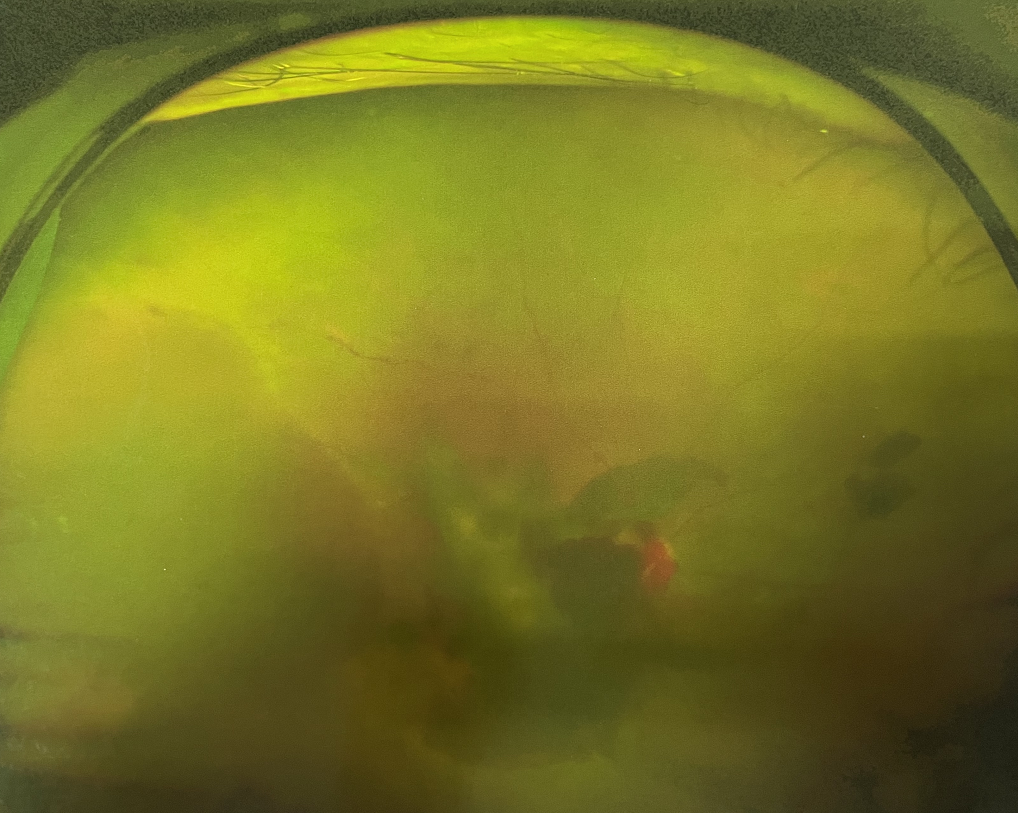

眼底出血多指玻璃體內,眼睛更深處的視網膜出血。通常情況下,肉眼難以發(fā)現(xiàn)眼底出血,而且發(fā)病初期眼睛也無明顯癥狀,只有借助專業(yè)的眼底檢查儀器才能觀察到異樣。那么眼底出血嚴重嗎?

誘發(fā)眼底出血的原因眾多,常見的有全身性血管病和血液病、視網膜血管異常、機械性阻塞、炎癥性疾病或免疫復合物侵犯血管壁等。

眼底出血嚴重嗎?其中,“三高”患者、高度近視患者和滲出性或濕性老年黃斑變性患者是眼底出血的高發(fā)人群。

眼底出血嚴重嗎?對于已出現(xiàn)黃斑水腫、視網膜新生血管的患者,根據眼底血管造影、oct等檢查結果,給予玻璃體腔注射抗VEGF藥物及激光治療,可以減輕黃斑水腫,使視網膜新生血管消退,以免進一步發(fā)生玻璃體出血、視網膜脫離等嚴重并發(fā)癥的出現(xiàn)。對于玻璃體出血者,傳統(tǒng)認為玻璃體出血3-6個月不吸收再進行手術干預,但近年來因為顯微手術設備及玻璃體切割技術已非常成熟,故對于1個月不吸收的玻璃體出血者就可以考慮手術,即手術時機應該具體情況具體分析,因人而異。